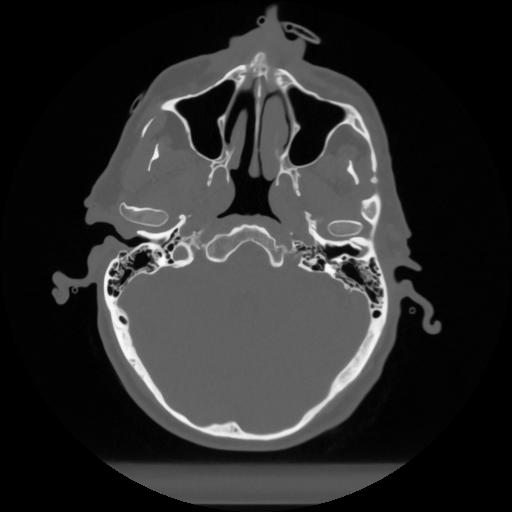

12 P.BLANDAS,,Vol,0.5,P.BLANDAS,,